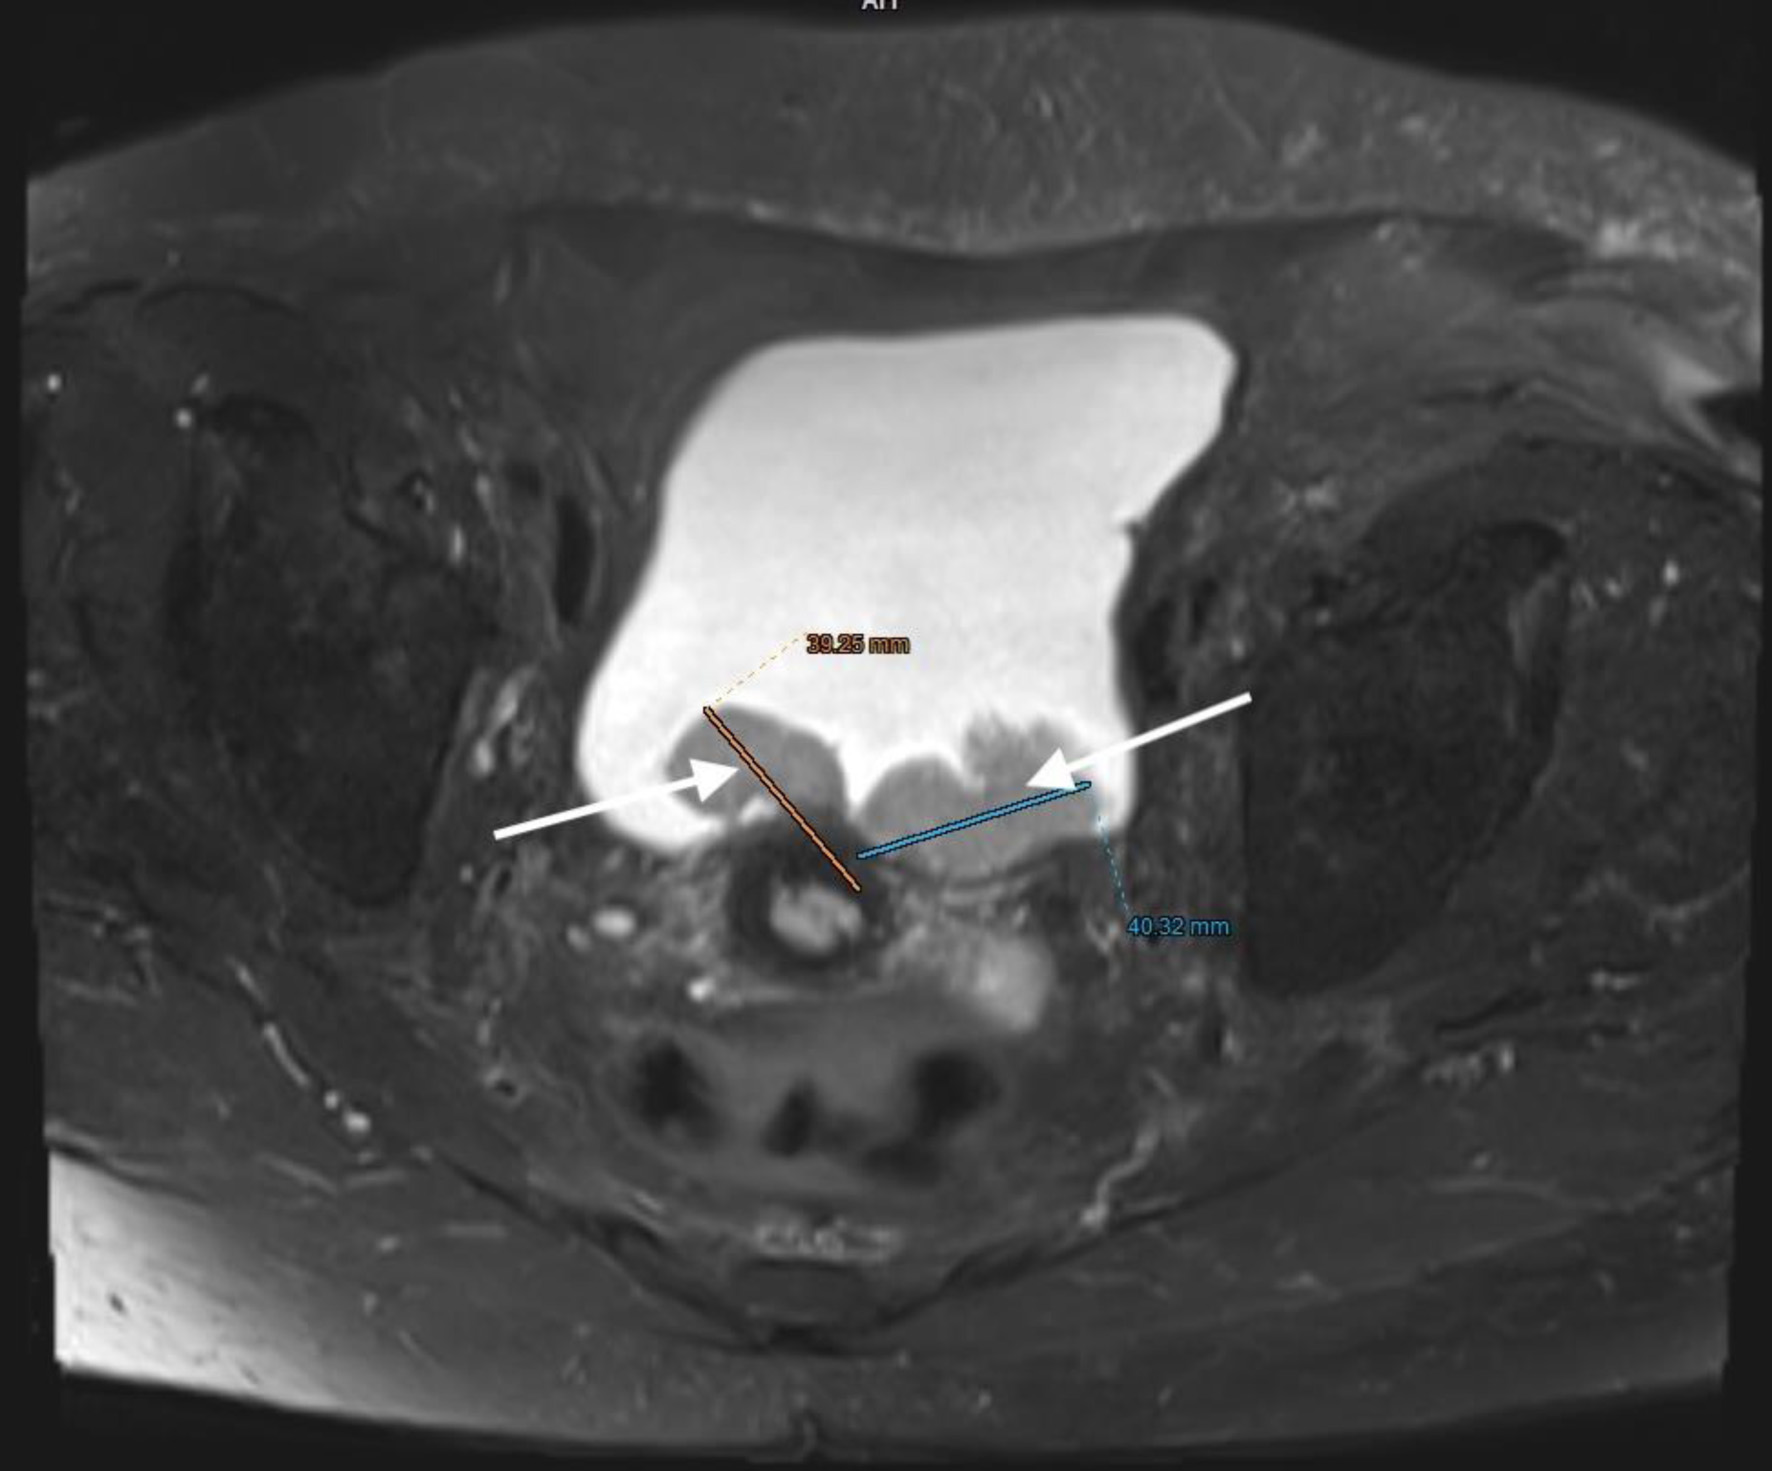

The patient, who had undergone a left nephroureterectomy 1 year earlier for urothelial carcinoma, presented again with suspected malignancy of the right upper urinary tract. Following urological consultation and instrumental evaluation (cystoscopy), urinary bladder tumors were detected, and the patient proceeded to further imaging assessment. Magnetic resonance imaging (MRI) of the upper abdomen revealed a tumor in the right kidney with invasion of the ureter and perirenal adipose tissue (Figs. 6 and 7). Lower abdominal MRI examination confirmed urinary bladder tumors with infiltration of the distal ureter and uterus (Figs. 811). Considering the patient’s clinical status, the potential aggressiveness of the malignancy, the absence of definitive histopathological confirmation of the new tumors (which could represent distinct lesions requiring separate pathological sampling), and the patient’s preference, no preoperative neoadjuvant therapy was administered. Surgery was therefore the only available therapeutic option, to which the patient provided full informed consent, despite her high-risk clinical profile and the complexity of the proposed high-risk surgical procedure. The postoperative histopathological report demonstrated high-grade renal urothelial carcinoma with contiguous extension to the ureter, urinary bladder, and bladder neck. Five of the 11 excised lymph nodes were metastatic, classifying the tumor as pT4N2Mx. Despite radiological evidence suggestive of uterine involvement, histopathological examination of the uterus and ovaries showed no malignancy; instead, polypoid endometrial hyperplasia and ovarian cysts were identified.

Figure 8. Lower abdominal magnetic resonance imaging (MRI) revealed a vegetative, infiltrative lesion invading the surrounding adipose tissue and occupying the urinary bladder cavity (arrow).

Figure 9. Lower abdominal magnetic resonance imaging (MRI) revealed a vegetative, infiltrative lesion invading the surrounding adipose tissue and occupying the urinary bladder cavity (arrows).